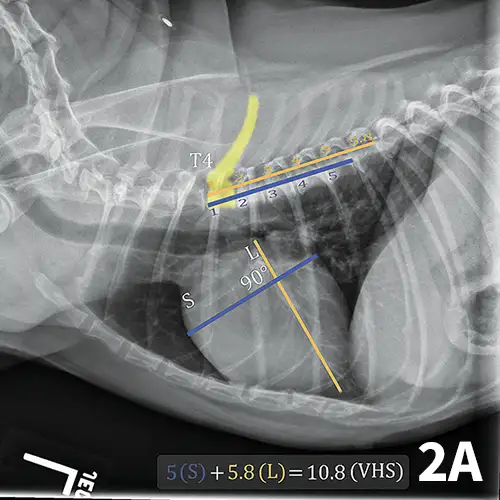

A lateral thoracic radiograph of a normal dog with measurements added to evaluate heart size compared to the thoracic vertebrae.

FIGURE 1

Illustration of VHS calculation in a normal dog. On a lateral radiograph, a line is drawn from the carina to the most ventral aspect of the heart. This line is the “L” or long axis line. A line is drawn perpendicular to the long axis at the widest portion of the heart, extending to the cranial and caudal borders. This is the short axis or “S” line. These lines are transposed using calipers extending along the spine from the cranial aspect of T4. The number of vertebrae traversed (rounded up to the nearest tenth) are added together for the VHS.

The ACVIM consensus statement on degenerative MVD recommends baseline thoracic radiography for dogs with a new murmur, then annually thereafter.6 For practitioners adhering to these guidelines, annual calculation of VHS and rate of change from previous imaging should become standard practice and may help identify those patients at higher risk of developing CHF in the coming year. Figure 2 illustrates annual radiographs taken in a patient with progressive cardiomegaly.

Progressive cardiomegaly noted on annual evaluations in a dog with MVD.